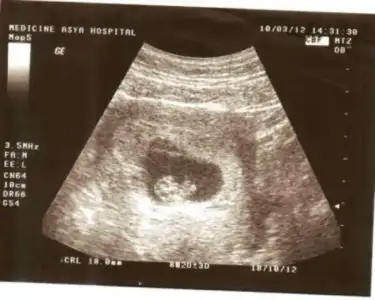

bugün sizlere bebişimin 8 haftalık ultrason resmini paylaşmak istedim:31:

Eki Görüntüle 367104

Eki Görüntüle 367105

kedersiz canım maşallahh bebişineee :nazar: :nazar: boyu ne kadardı ozamanda canım baktım ama ultrasonda ölçümü göremedim

doktor 1buçuk santimi geçmiş demişti

ultrason kağıdında yazmıyo ama